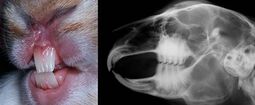

Overgrown teeth roots

In other cases, overgrown teeth roots can be the cause of many health issues such as weepy eyes, sneezing, and anorexia. When severe, teeth roots can grow into the eyes and cheeks and even break the skin. This condition cannot usually be diagnosed with a visual check by a veterinarian and requires more advanced imaging such as radiographs and CT scans.

Overgrown teeth roots should be treated with pain management and ultimately surgical removal if appropriate. More information about rabbit teeth removal can be found in the Malocclusion article.